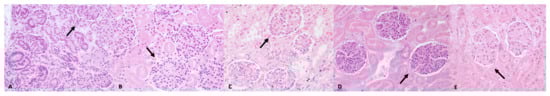

3.1. Histological Examination

3.2. Immunohistochemical Examination